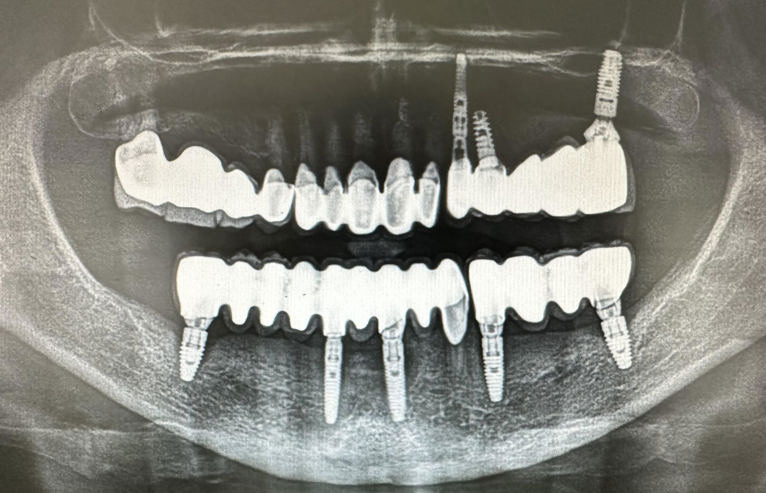

Foto: Dental Centar Jelić

Postupak se izvodi u lokalnoj anesteziji i potpuno je bezbolan. Ukoliko je potrebo ugraditi više implantata, ugrađuju se istovremeno u jednoj posjeti. Nakon 3 do 4 mjeseca vrši se kontrola učvršćivanja i pristupa se izradi keramičkog mosta ili krunice.